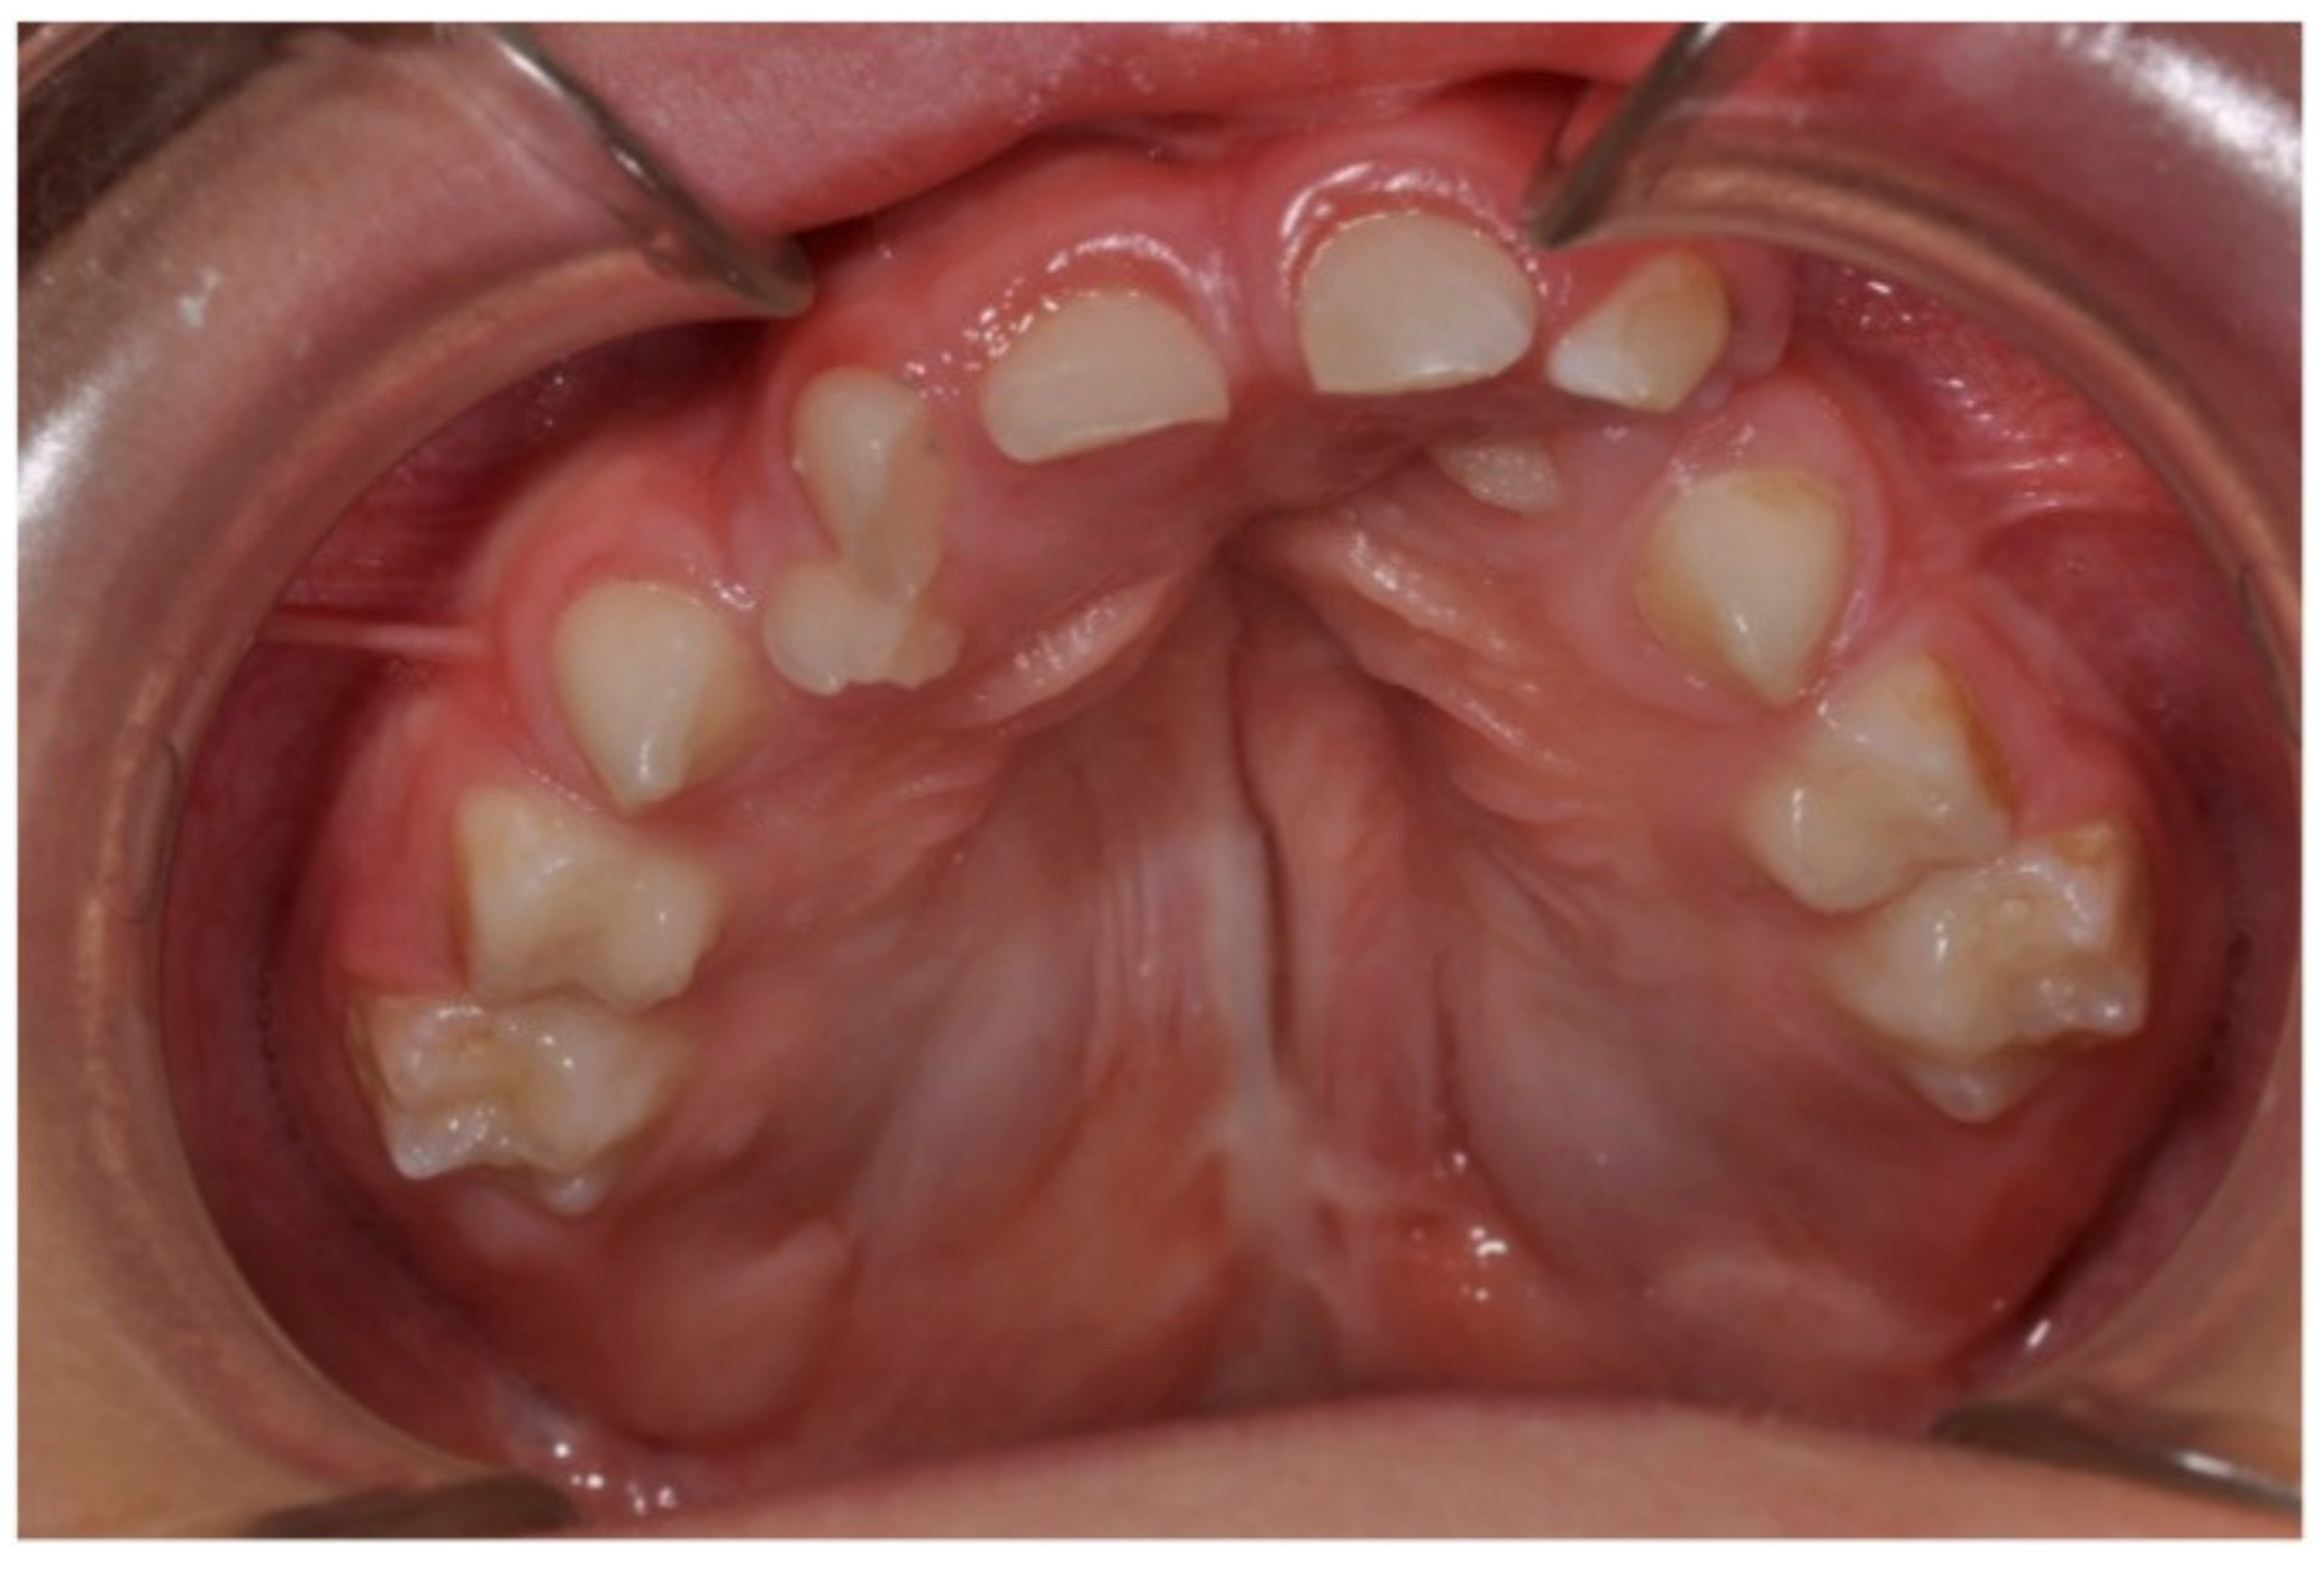

3.2. Pediatric Dentistry Specialist Management of Dental Anomalies in Children with CLP